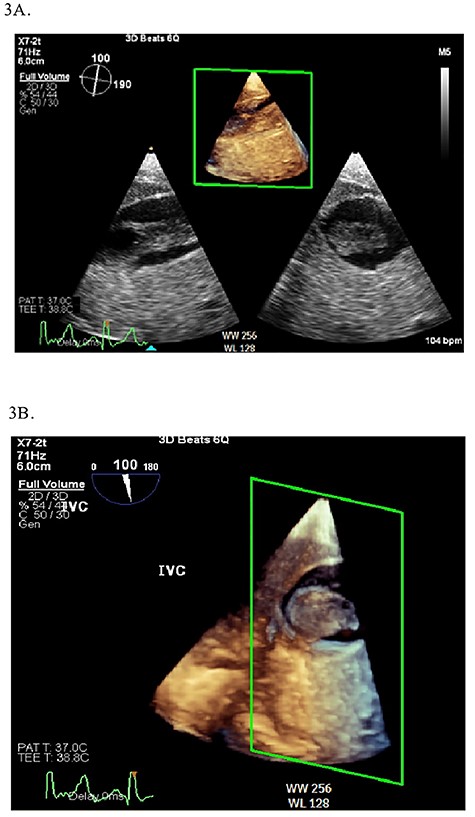

Continuous intraoperative transesophageal echocardiography (TEE) was performed. Postinduction TEE showed a large mobile mass of heterogeneous echogenicity in the RA abutting the tricuspid valve, mild tricuspid insufficiency, occlusive thrombus in the IVC and LV ejection fraction of 40% (Figs 2 and 3; Supplementary Materials S1 and S2). Given the location, size and mobility of the mass in the RA, the decision was made to remove it on CPB to minimize the risk of large embolus and significant blood loss. During the prebypass period, following laparotomy and drainage of abdominal ascites, the patient required significant colloid repletion with 5% albumin and blood products for hypotension, underfilled LV on TEE and low central venous pressure.

(A) Midesophageal four chamber TEE view showing large mobile mass of heterogeneous echogenicity in the RA. (B) Another view of the RA mass in a midesophageal bicaval view. (C) 3D illustration of the RA mass.